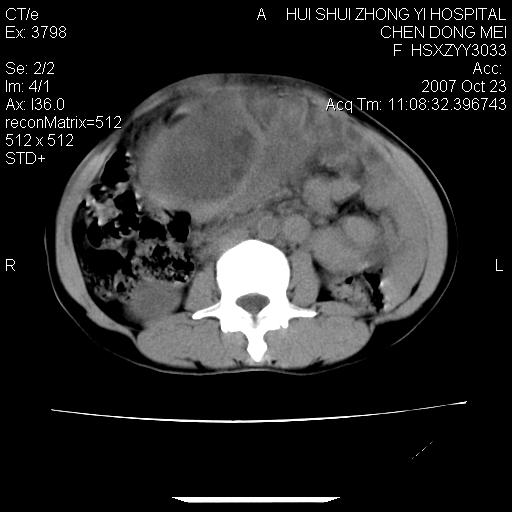

标题: CT10156:女.43岁,发现中下腹部包都块2年

发现中下腹部包都块2年。2年来月经不规律。

腹腔巨大软组织密度影,边缘光滑,包膜完整,内囊变坏死。腹膜后及盆腔内淋巴结肿大。结合病史考虑卵巢癌可能性大。

病变巨大,呈囊实性改变,包膜较厚且完整,内见分膈,周围脏器明显受压移位,病变与左侧附件关系密切,考虑来源左侧附件的囊腺瘤,不除外癌变可能;畸胎瘤可能性较小。

病变巨大,呈囊实性改变,包膜较厚且完整,内见分膈,周围脏器明显受压移位,病变与左侧附件关系密切,考虑来源左侧附件的囊腺瘤,盆腔内见肿大淋巴结,不除外癌变可能。